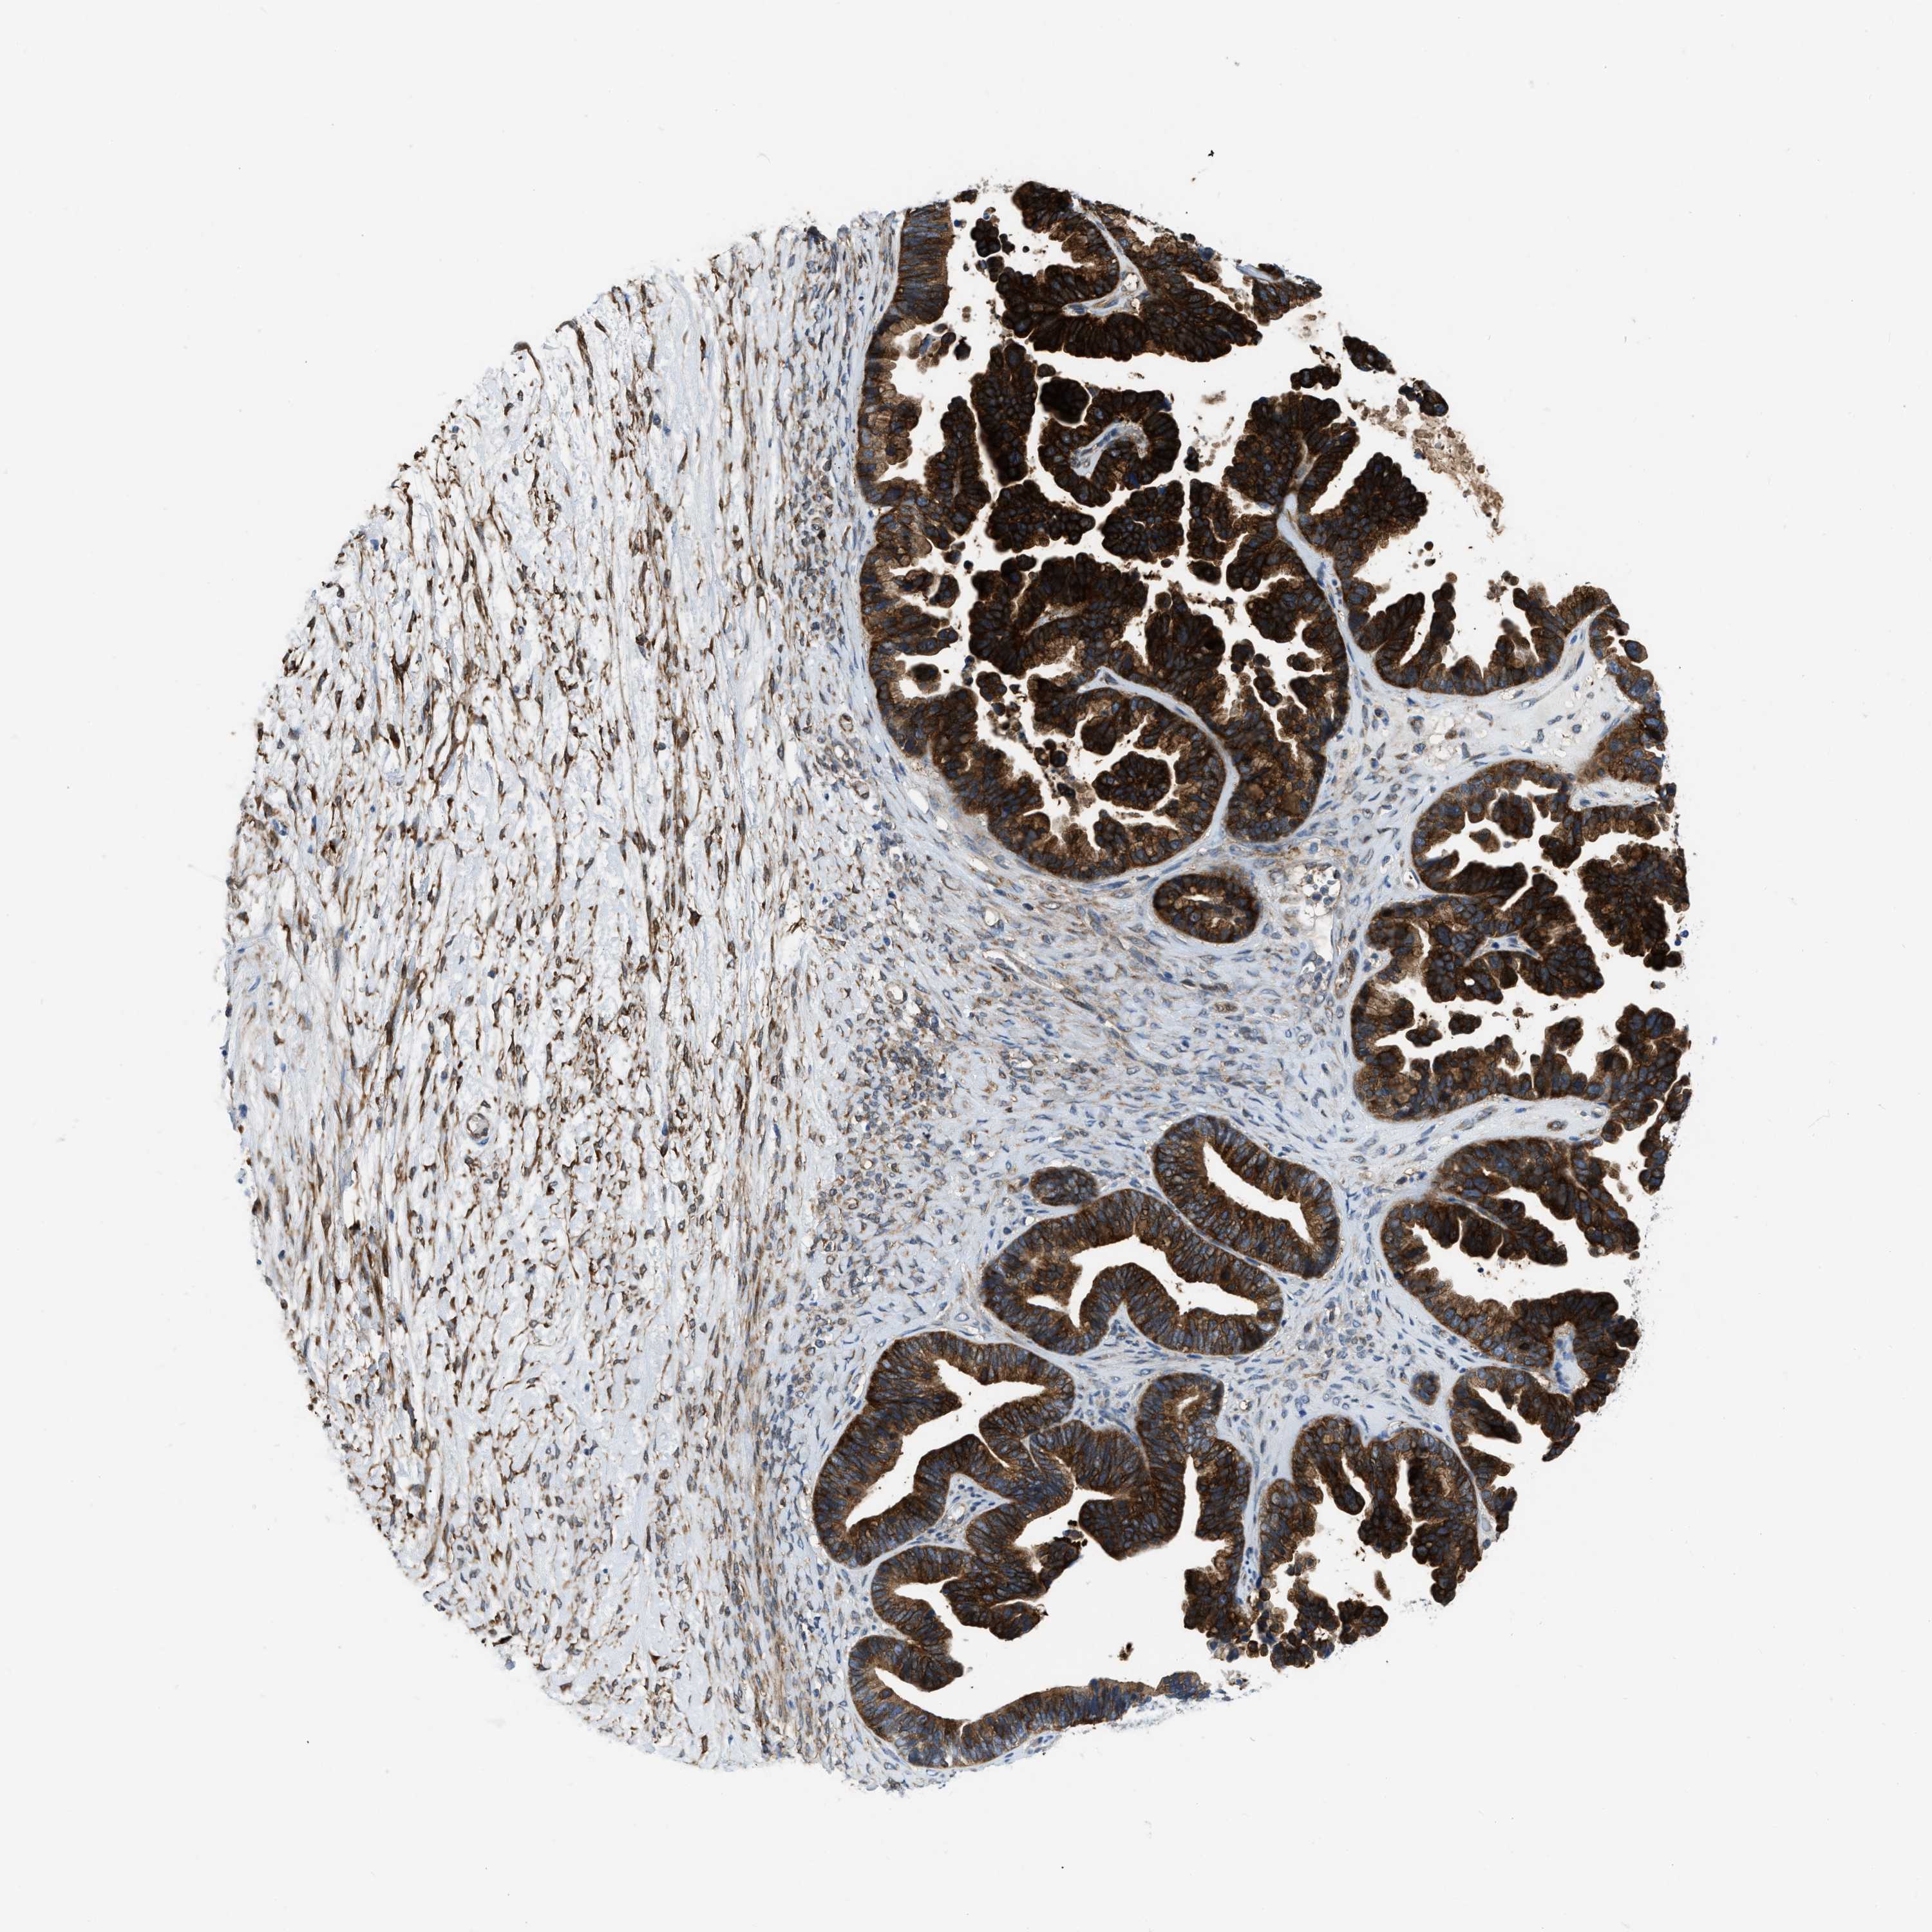

OVARIAN CANCER - Protein expressioni

A mouse-over function shows sample information and annotation data. Click on an image to view it in a full screen mode. Samples can be filtered based on level of antibody staining by selecting one or several of the following categories: high, medium, low and not detected. The assay and annotation is described here.

Note that samples used for immunohistochemistry by the Human Protein Atlas do not correspond to samples in the TCGA dataset.

Antibody stainingi

Antibody staining in the annotated cell types in the current human tissue is reported as not detected, low, medium, or high, based on conventional immunohistochemistry profiling in selected tissues. This score is based on the combination of the staining intensity and fraction of stained cells.

Each image is clickable and will lead to virtual microscopy that enables deeper exploration of all samples and also displays staining intensity scores, fraction scores and subcellular localization as well as patient and tissue information for each sample.

Antibody HPA018257

Staining

High

Medium

Low

Not detected

Intensity

Strong

Moderate

Weak

Negative

Quantity

>75%

75%-25%

<25%

None

Location

Nuclear

Cytoplasmic/membranous

Cytoplasmic/membranous,nuclear

Cystadenocarcinoma, serous, NOS

Carcinoma, endometroid

Cystadenocarcinoma, mucinous, NOS

Carcinoma, NOS